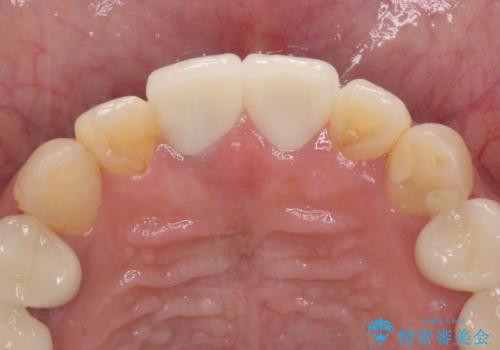

気になる部分を全て治療 総合歯科治療で口腔内環境改善

- 右下の欠損部の治療を希望して来院された患者様です。

部分矯正を行った後にインプラント埋入と手前の歯の根管治療を行い、その後補綴治療を行うこととしました。

治療途中より、上の歯や反対側の銀歯、上顎前歯の色合いや下顎前歯のデコボコが気になってきたため、全てを治療することとしました。